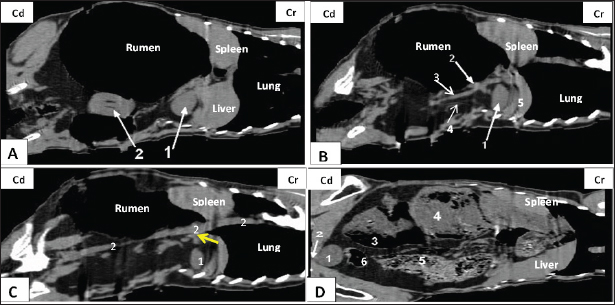

Both kidneys were readily distinguishable based on their morphology and associations in both anatomical and CT examinations (Figs. 2, 4). In both the transverse and dorsal planes of the CT scan, the objects exhibited a spherical to bean-shaped morphology.

On CT, both kidneys exhibited hypoechoic structures characterized by an anechoic hilus. A clear differentiation was observed between the cortex, medulla, and adjacent perirenal fat, particularly in the frozen sections.

On CT, both kidneys appeared ovoid and sharply demarcated with homogenous renal parenchyma. There was no sharp demarcation between the cortex and medulla, although the cortex was slightly denser than the medulla.

A dorsal-plane CT scan revealed the presence of the right renal vein, which extended from the right kidney toward the caudal vena cava (Fig. 4). Both transverse and dorsal plane CT scans revealed the presence of the right renal artery, which originates from the aorta and extends toward the right kidney (Figs. 2, 4). Following its entry into the renal hilus (Fig. 2), the structure underwent bifurcation into its dorsal and ventral branches. In the dorsal-plane CT scan, the right ureter was positioned dorsally adjacent to the caudal vena cava, extending toward the urinary bladder. The lumen was smaller in size compared with the renal vein (Fig. 4).

The egress of the left ureter from the left renal hilus was observed in the transverse CT image (Fig. 2). On transverse- and dorsal-plane CT scans (Figs. 3, 4), the urinary bladder may be identified at the sacrum level on the pelvic floor, located beneath the uterus and rectum. A dorsal-plane CT scan revealed the presence of the urethra exiting the urine bladder in a caudal direction (Fig. 4).

Fig. 4. Representative computed tomography image of the goat trunk in the dorsal plane. Panel (A): 1-Right kidney; 2-Left kidney. Panel (B): 1-Right kidney; 2-Right renal vein; 3-Caudal vena cava; 4-Right ureter; and 5- caudate lobe of the liver. Panel (C): 1-Right kidney; 2-Aorta. Panel (D): (1) urinary bladder; (2) urethra; (3) intra-ruminal gases; (4) rumen; (5) intestinal; (6) colon.

Based on the echogenicity analysis, the kidneys exhibited intermediate echogenicity (gray) in conjunction with the presence of anechoic (black) perirenal fat in their vicinity. The renal pelvis had a darker hue (black) than the renal parenchyma, which can be attributed to the presence of adipose tissue. The distinctive morphology facilitated the recognition of the kidneys in the CT scan examination. These findings are in the same line with previous work on goats(Braun et al., 2011) and humans (Sagel et al., 2002).